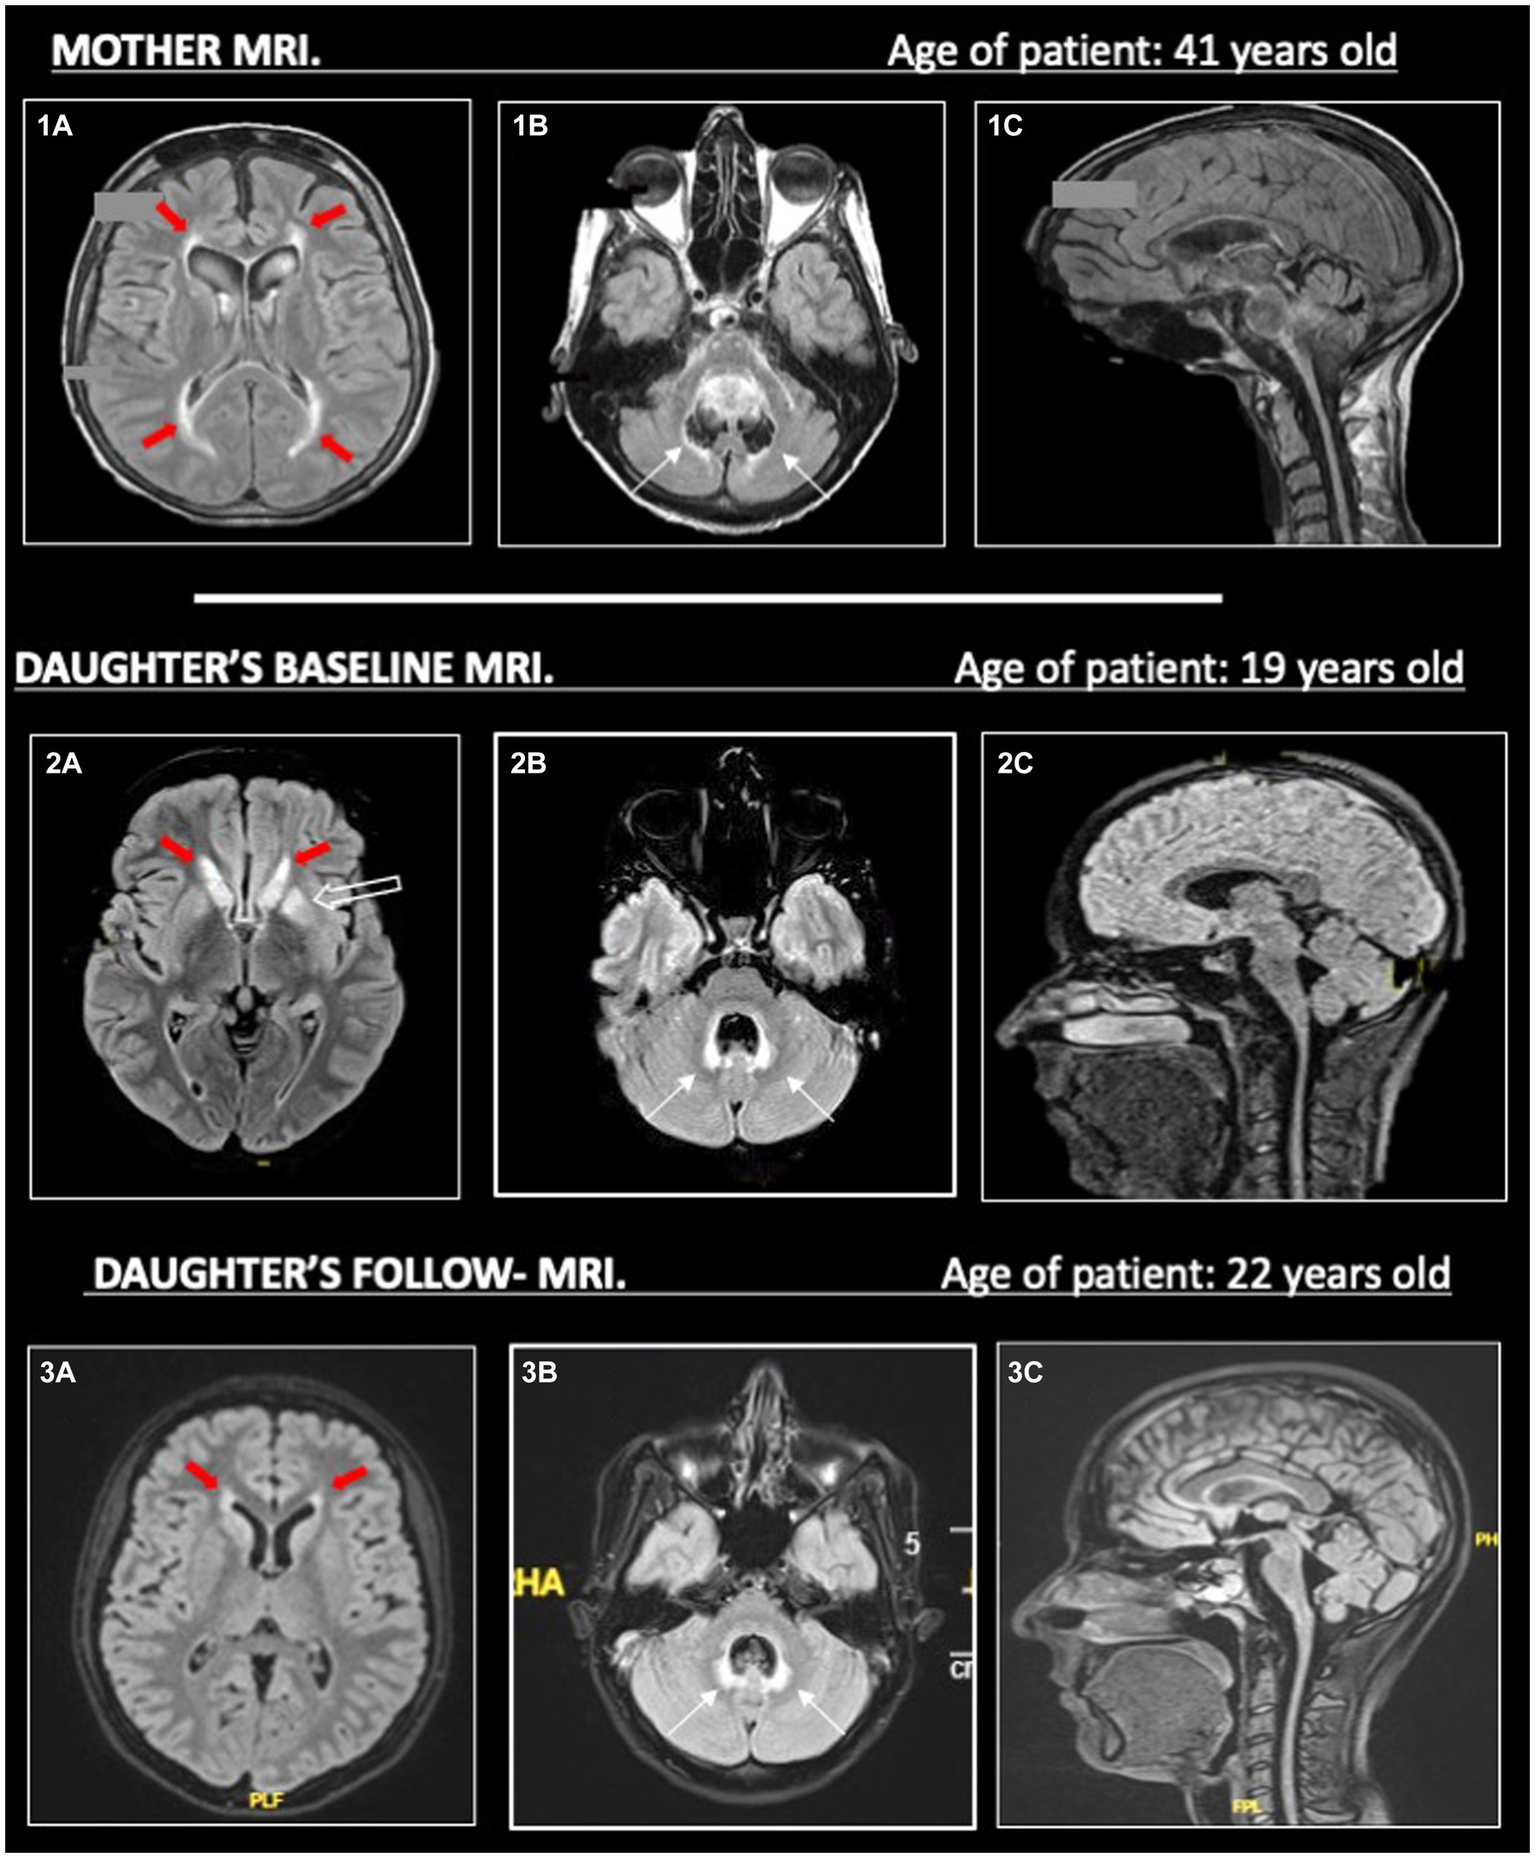

In the meantime, the patient performed further exams, including a brain and spinal cord MRI. The MRI evidenced limited T2-hyperintensities involving the periventricular and temporal insular white matter in both hemispheres, and, more interestingly, the T2-hyperintensities also involved basal ganglia, middle cerebellar peduncles, and the area around the IV ventricle; no enhancement was identified in these areas. Moreover, it showed cerebellar vermal and spinal cord atrophy (Figure 2).

On the left (1a, 2a, 3a), we show T2-hyperintense symmetric periventricular lesions (red-filled arrows) in both mother and daughter. In (2a), we can see T2-hyperintensities in the basal ganglia (empty arrow) of the daughter, less evident in her MRI follow-up in 2023 (3a). On the central column (1b, 2b, 3b), widespread atrophy of the cerebellar vermis is evident in both mother and daughter (1b, 2b), without evident worsening in the follow-up MRI (3b) in the daughter. T2-hyperintensities around the IV ventricle (thin black arrows) are more pronounced in the daughter than the mother, maybe due to a higher cerebellar vermis atrophy. On the right (1c, 2c, 3c), in the sagittal images, we can see prominent atrophy of the cerebellum, brainstem (with spare of pons) and cervical spinal cord. All MRI sequences are FLAIR, apart from (1c) (T1).

At this point, we obtained a mother’s MRI, performed at the age of 41 years old. This MRI evidenced white matter abnormalities around the IV ventricle, more limited white matter abnormalities in the supratentorial periventricular area, and pial T2-hyperintensities were described in the brainstem and cerebellum; a severe atrophy of the brainstem, cerebellum (especially the vermis), and cervical spinal cord was described (Figure 2). However, the mother’s MRI accounted for the advanced phase of the disease, and no previous imaging was available.

The diagnostic process was further complicated by the incomplete knowledge of the patient’s pedigree and the complex neuroimaging patterns in the patient and her mother, taken in different stages of the disease. As illustrated in Figure 2, the predominant atrophy of the brainstem with a spare of pons (tadpole atrophy), the atrophy of the cerebellum and spinal cord, the pial and sub-pial alterations of the brainstem, and the few white matter abnormalities may have suggested the possibility of a type II AxD.